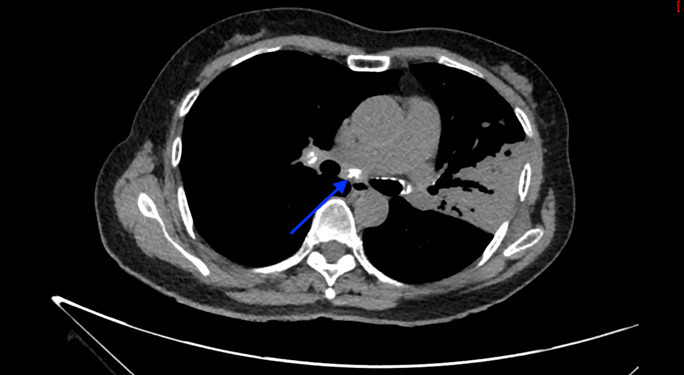

Un scanner thoracique est finalement réalisé devant cette toux chronique et l’altération de l’état général, dont voici quelques coupes :

Figure 3 (Jacques Durin, La Revue du Praticien)

Flèche bleue.

Le compte-rendu de radiologie décrit un aspect de pneumopathie lobaire supérieure gauche associée à des micronodules péri-bronchiolaires et des adénopathies médiastino-hilaires calcifiées.